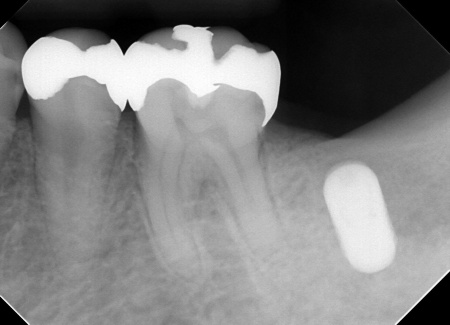

・右上奥歯

一番奥の歯が欠損し、その手前の歯は詰め物の内部で虫歯が進行しています。

・右下奥歯3本

噛む面や歯間に虫歯が見られ、歯が欠けている部分もあります。